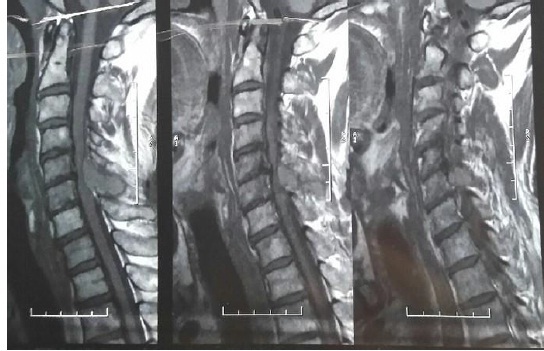

Мягкотканые образования в костях и мягких тканях выявлялись по данным компьютерной томографии (КТ) и магнитно-резонансной томографии (МРТ) (рис. 1–3). Эти инструментальные методы обследования позволили подтвердить наличие плазмоцитомы у данной категории больных (в костях грудной клетки, в позвоночнике, в глазнице).

Рис. 2. Экстрадуральное образование на уровне С5 позвонка с прорастанием в спинномозговой канал при магнитно-резонансной томографии шейного отдела позвоночника